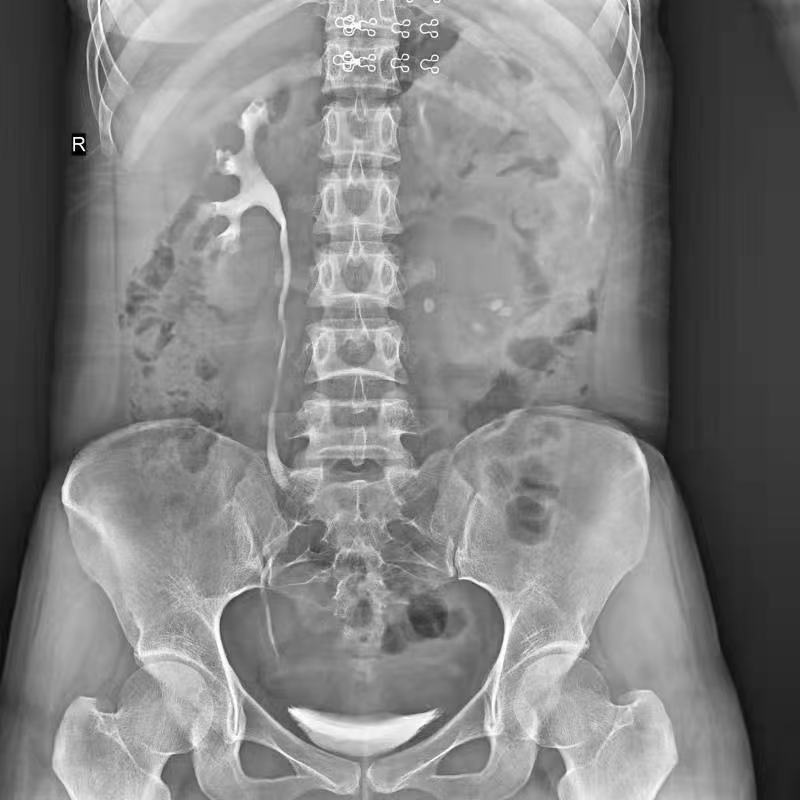

IMG-145314-0001

盆骨 (2)